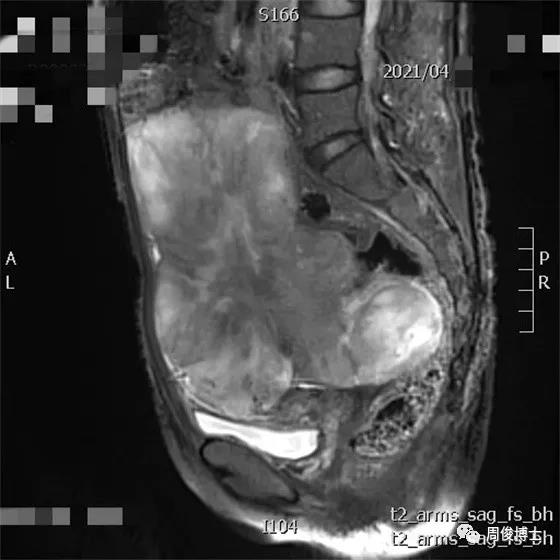

2021年3月,治療前基線,腫瘤巨大,腸道擠成一條線,子宮被壓成小蘿卜干,還有腹水

治療一個半月后,腫瘤退縮,腹水消失,大腸形態(tài)恢復(fù),可見腸內(nèi)容物。

治療七個月后,腫瘤繼續(xù)縮小,腸道通暢,子宮大小恢復(fù)正常,肌肉脂肪豐滿